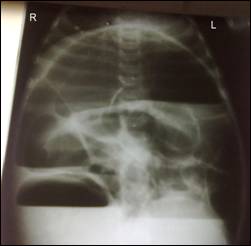

Image 1: Xray abdomen erect posture showing air fluid levels indicating intestinal obstruction.